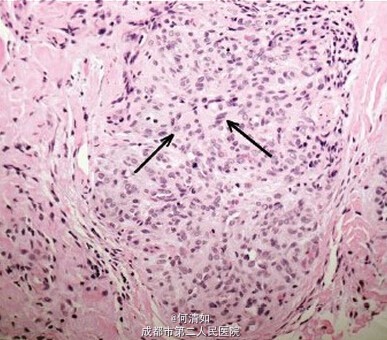

诊断:上皮样血管内皮瘤 处理:全切

经2年以上随访,无局部复发或远处转移。 上皮样血管内皮瘤是一种罕见的血管瘤,被认为是在上皮样血管瘤(良性)和上皮样血管肉瘤(高度恶性)中间。它可以影响许多器官如肝、骨、肺、皮肤、软组织,而眼睑累及是极为罕见的。 因为眼睑上皮样血管内皮瘤是一种低度恶性病变,其复发率高(没有完全切除活检),但很少转移。此例患者病损完整切除,不需要其他局部切除术治疗。此外,辅助放疗或化疗疗效有待进一步证明。 临床表现类似霰粒肿,易误诊。